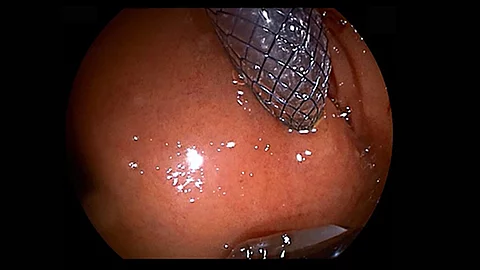

Endoskopisches LehrvideoTransbulbäre Drainage der Gallenwege mittels EUS

Eine 57-jährige Patientin stellt sich mit Pankreaskopfkarzinom und bekannter DHC-Stenose vor. Ein Wechsel der zuvor eingebrachten Prothese ist wegen Infiltration des Duodenums nicht mehr möglich. Prinzipiell kann man bei solchen Patienten eine EUS-Drainage der Gallenwege durchführen. In diesem Fall erfolgt die Punktion im Bereich der Hinterkreuzung…